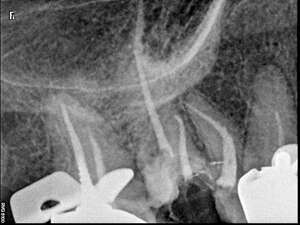

Avant